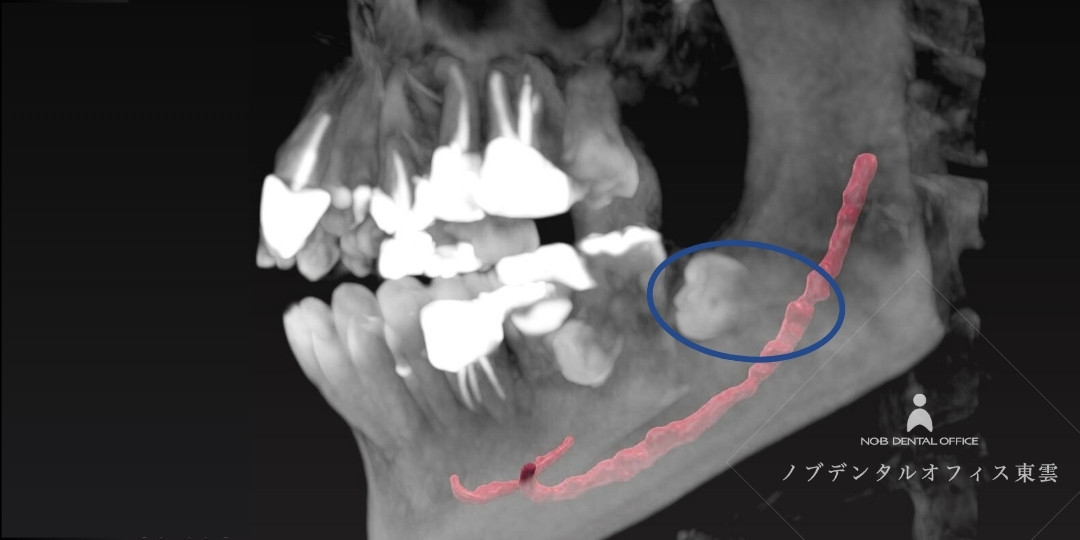

必要に応じて、親知らずの根の複雑な形状や、近くを通る神経との距離などを3次元で正確に診査します。

歯科用CTでは、親知らず(青い丸)と、下顎を通る太い神経(赤い線)の3次元的な位置関係を明確に診査できます。